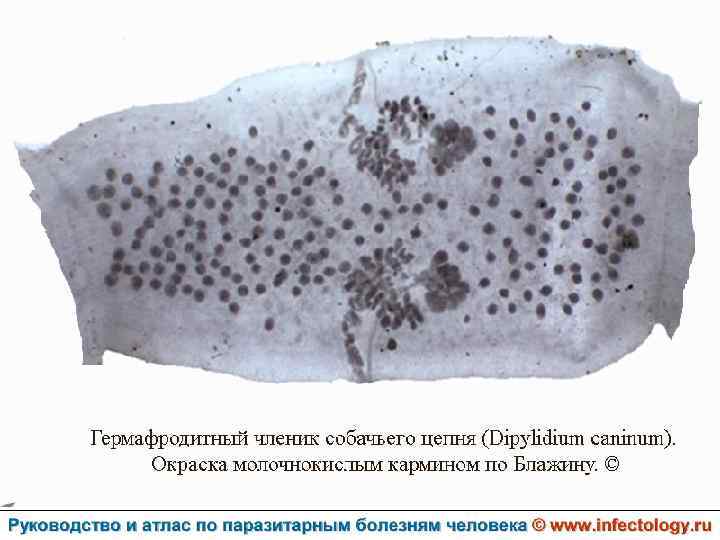

Дипилидиоз (шифр по МКБ 10 – B 71. 1) зоонозный биогельминтоз, характеризующийся аллергизацией организма и нарушением функций пищеварительного тракта.